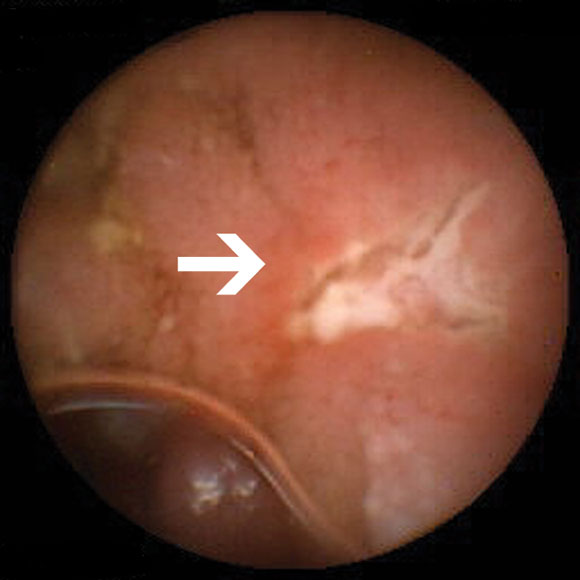

In 47 patients with OGB, abnormal findings (Box 2A) were detected in 32 (68%). Four had abnormalities detected in the stomach, and one in the caecum. Eight had abnormalities judged to be within reach of push enteroscopy. Eighteen of the 47 (38%) patients had a change in management as a result of capsule endoscopy (Box 3).

Of the nine patients referred for investigation of small-bowel Crohn's disease, none had been taking non-steroidal anti-inflammatory drugs (NSAIDs) before onset of their symptoms. Small-bowel erosions or ulcers (Box 2B) were seen in seven of these nine patients. Enteroclysis demonstrated mucosal irregularity in two of the seven patients with abnormal findings on capsule endoscopy. Management was changed in five of the nine patients. One patient was lost to follow-up. Changes in management are summarised in Box 4.